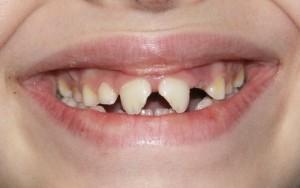

Da un punto di vista “classificativo” i traumi dentali possono andare dalla semplice infrazione coronale alla completa avulsione di uno o più elementi; l’evenienza più frequente è la frattura coronale, con o senza esposizione della polpa dentale. (foto 1)

Foto 1

Fondamentale è, sempre, la tempestiva visita dal dentista; in molti casi infatti, se il trauma ha comportato il distacco di un unico frammento, questo può essere reincollato al dente, sempre che la procedura avvenga nelle prime ore dopo il trauma. Se invece il

Foto 2

frammento non è unico o non è stato ritrovato è necessario provvedere alla ricostruzione delle parti mancanti. (foto 2)